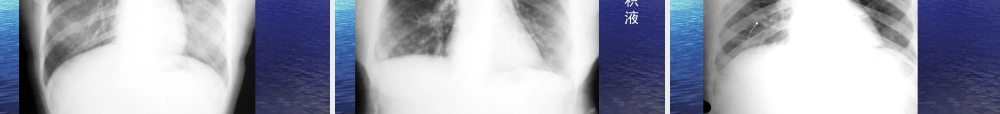

胸部普通胸部普通XX线影像诊断线影像诊断学学DiagnosticimageologyofchestdiseasesDiagnosticimageologyofchestdiseases第一章呼第一章呼吸系统吸系统RespiratorysysteRespiratorysystemm特点:特点:含有空气,良好自然对比;含有空气,良好自然对比;病变密度增加或降低;病变密度增加或降低;能直接显示病变部位、范围和性质;能直接显示病变部位、范围和性质;方法简单、应用广泛;方法简单、应用广泛;随访:随访:<<3mm3mm孤立病灶;大叶性肺炎早期以及病灶孤立病灶;大叶性肺炎早期以及病灶被遮盖被遮盖,,检查受限。检查受限。第一节第一节XX线检查技术线检查技术TechniquesofX-rayTechniquesofX-ray常规常规XX线技术;线技术;胸部胸部CTCT技术;技术;胸部胸部MRIMRI技术;技术;胸部超声技术。胸部超声技术。一、普通检查一、普通检查ConventionalexaminationConventionalexamination((一一))胸部透视胸部透视(chestfluoroscopy)(chestfluoroscopy)((二)二)胸部摄影胸部摄影::(chestradiography)(chestradiography)–后前位后前位,,前后位前后位((一般应用于床头摄影一般应用于床头摄影),),侧位侧位–前弓位:肺尖部、锁肋骨重叠病及中叶病变前弓位:肺尖部、锁肋骨重叠病及中叶病变–侧卧水平方向后前位:少量积液、肺下积液侧卧水平方向后前位:少量积液、肺下积液透视时,荧光屏上的影像以黑色表示高密度物质;以白色透亮表示低密度物质(三)、(三)、数字化数字化XX线摄影线摄影包括包括CRCR和和DR,DR,优点:优点:图像清晰度提高;图像清晰度提高;XX线的接受剂量降低;线的接受剂量降低;影像存储传输(影像存储传输(PACS)PACS)及远程医疗服务;及远程医疗服务;图像后处理,图片校正及减少重拍率。图像后处理,图片校正及减少重拍率。CRCR(computedradiography,CR)(computedradiography,CR)摄像板摄像板(IP)(IP)代替代替XX线胶片。线胶片。XX线影像线影像→→读取装置读取装置→→数字信号数字信号→→后处理后处理→→数字信号数字信号→→光信号光信号→→激光照相机激光照相机→→CRCR像片。像片。高曝光宽容度,低辐射及可调节显示窗高曝光宽容度,低辐射及可调节显示窗。。DRDR(digitalradiography,DR)(digitalradiography,DR)专用计算机直接读取感应介质记录到的专用计算机直接读取感应介质记录到的XX线影像信息线影像信息→→数字化图像重放和记录。数字化图像重放和记录。资料快速、准确光速传输,可行...